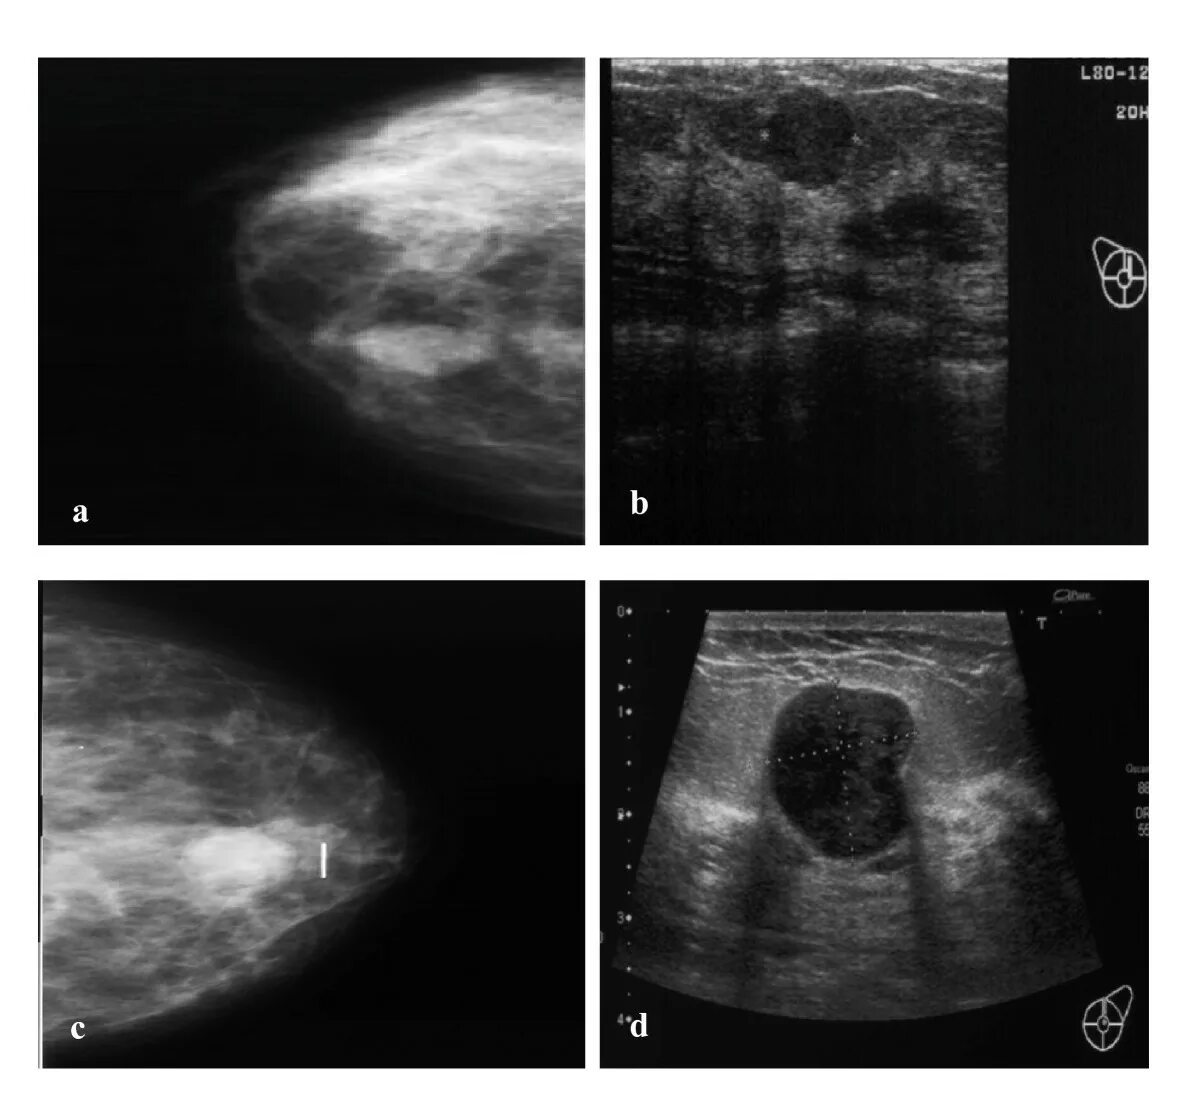

Линейный фиброз молочных желез